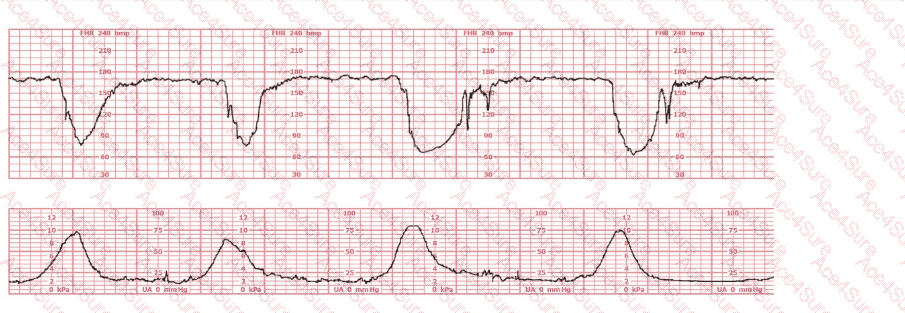

The fetal heart rate tracing demonstrates recurrent deep variable decelerations with a rapid drop in FHR, a V-shaped pattern, and slow return to baseline. These are classic signs of cord compression. According to NCC, AWHONN, Miller, Menihan, and Simpson, recurrent variable decelerations require immediate intrauterine resuscitative interventions before any decision regarding operative birth.

The cervix has remained unchanged at 5 cm for 3 hours (a prolonged latent or early active labor pattern), but the fetal tracing shows Category II—recurrent variable decelerations. Category II dictates corrective action, not immediate delivery unless it progresses to Category III.